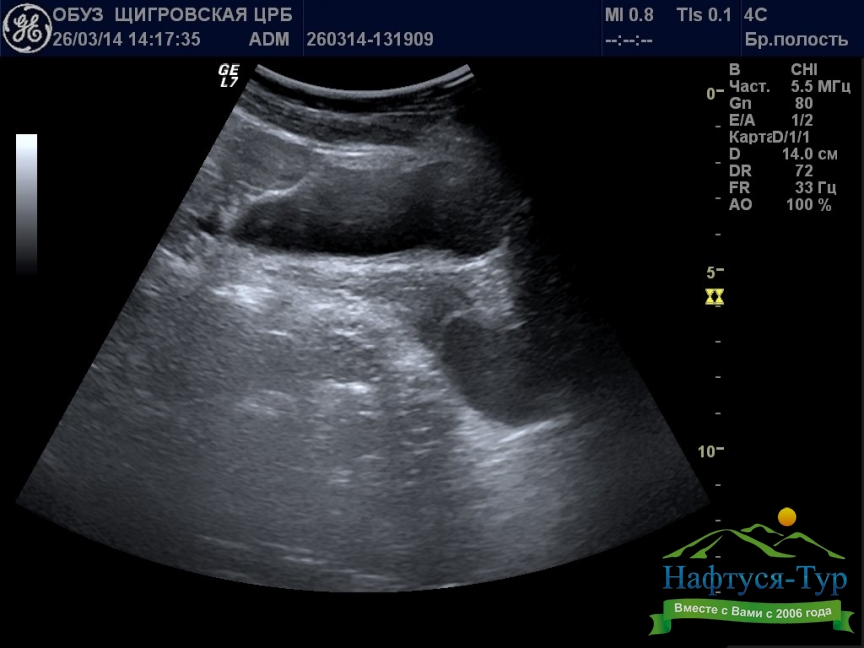

Ультразвуковое исследование (УЗИ, сонография) – неинвазивная диагностическая процедура, основанная на использовании акустических волн ультразвукового (выше порога слышимости для человека) диапазона. Используемая в санаториях техника для проведения УЗИ состоит из генератора и датчика. Генерируемые звуковые волны проникают в глубину тканей человека, при этом различные по типу ткани и инородные образования в разной степени отражают ультразвук. Отраженные волны улавливаются датчиком аппарата, накопленная информация обрабатывается компьютером, что позволяет сформировать изображение исследуемого органа.Отметим, что многие санатории имеют самые современные модели аппаратов для проведения УЗИ, в частности, позволяющие получать трехмерные и даже 4D (в динамике) изображения. Наиболее часто данный вид исследований назначают при диагностике мочекаменной и желчнокаменной болезни, заболеваниях почек, гипертонии, стенокардии.